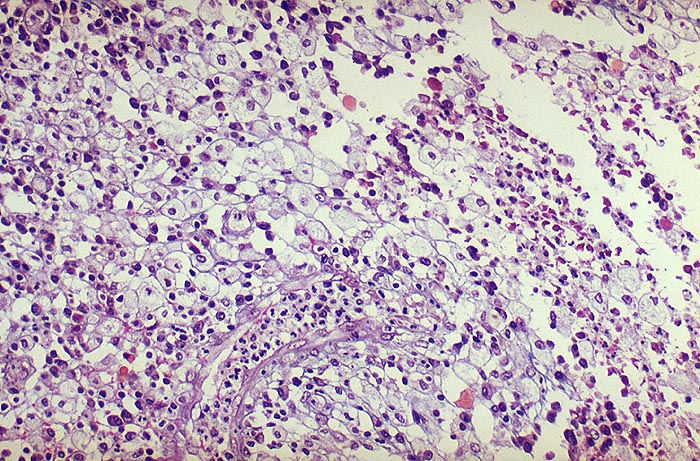

Infektiös eitrige Entzündungen der Niere sind erkennbar an einer Leukozyturie und Granulozytenzylindern. Gelegentlich können eosinophile Granulozyten auftreten.

Bei der Sonderform der xanthogranulomatösen Pyelonephritis ist das Urinsediment oft stark hämorrhagisch und entzündlich verändert und kann Schaumzellen enthalten. Der erste Fall zeigt eine akute eitrige Pyelonephritis. Der zweite Fall eine xanthogranulomatöse Pyelonephritis.